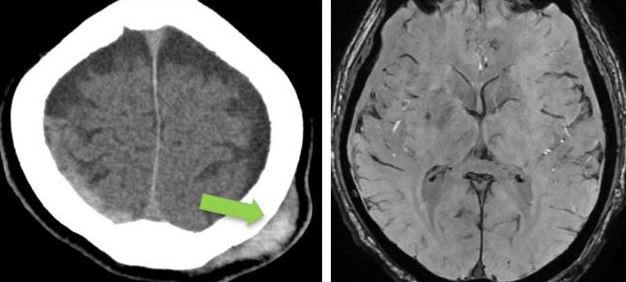

- CT brain – 11 June. Day 2 post mild head injury (after second fall).

Bilateral fronto- parietal hypodense subdural hemorrhage / effusion widest at frontal region, right measures 10 mm keft measures 13 mm in thickness.

There is hyperdense component seen at right parietal region (9 mm in thickness). Mild enhancement of the sulci bilaterally.

Gray-white matter differentiation fairly preserved.

No hydrocephalus.

No skull fracture.

Left parietal scalp swelling.

Impression: Bilateral fronto-parietal subdural hemorrhage as described.